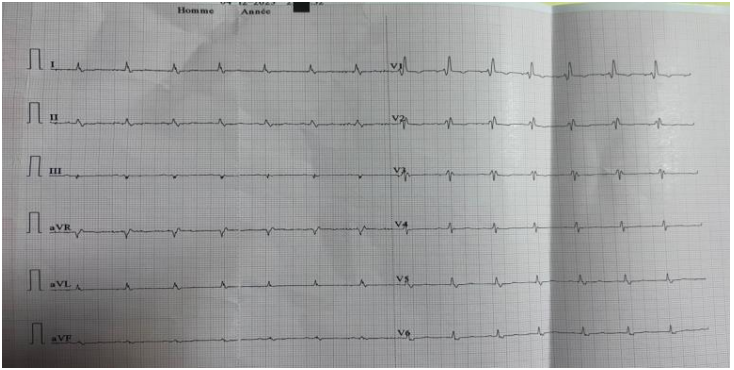

The electrocardiogram showed peripheral microvoltage and right bundle branch block (figure 1).

Figure 1: diffuse low voltage with right bundle branch block